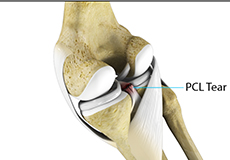

PCL Injuries

Posterior cruciate ligament (PCL), one of the four major ligaments of the knee, is situated at the back of the knee. It connects the thighbone (femur) to the shinbone (tibia). The PCL limits the backward motion of the shinbone.